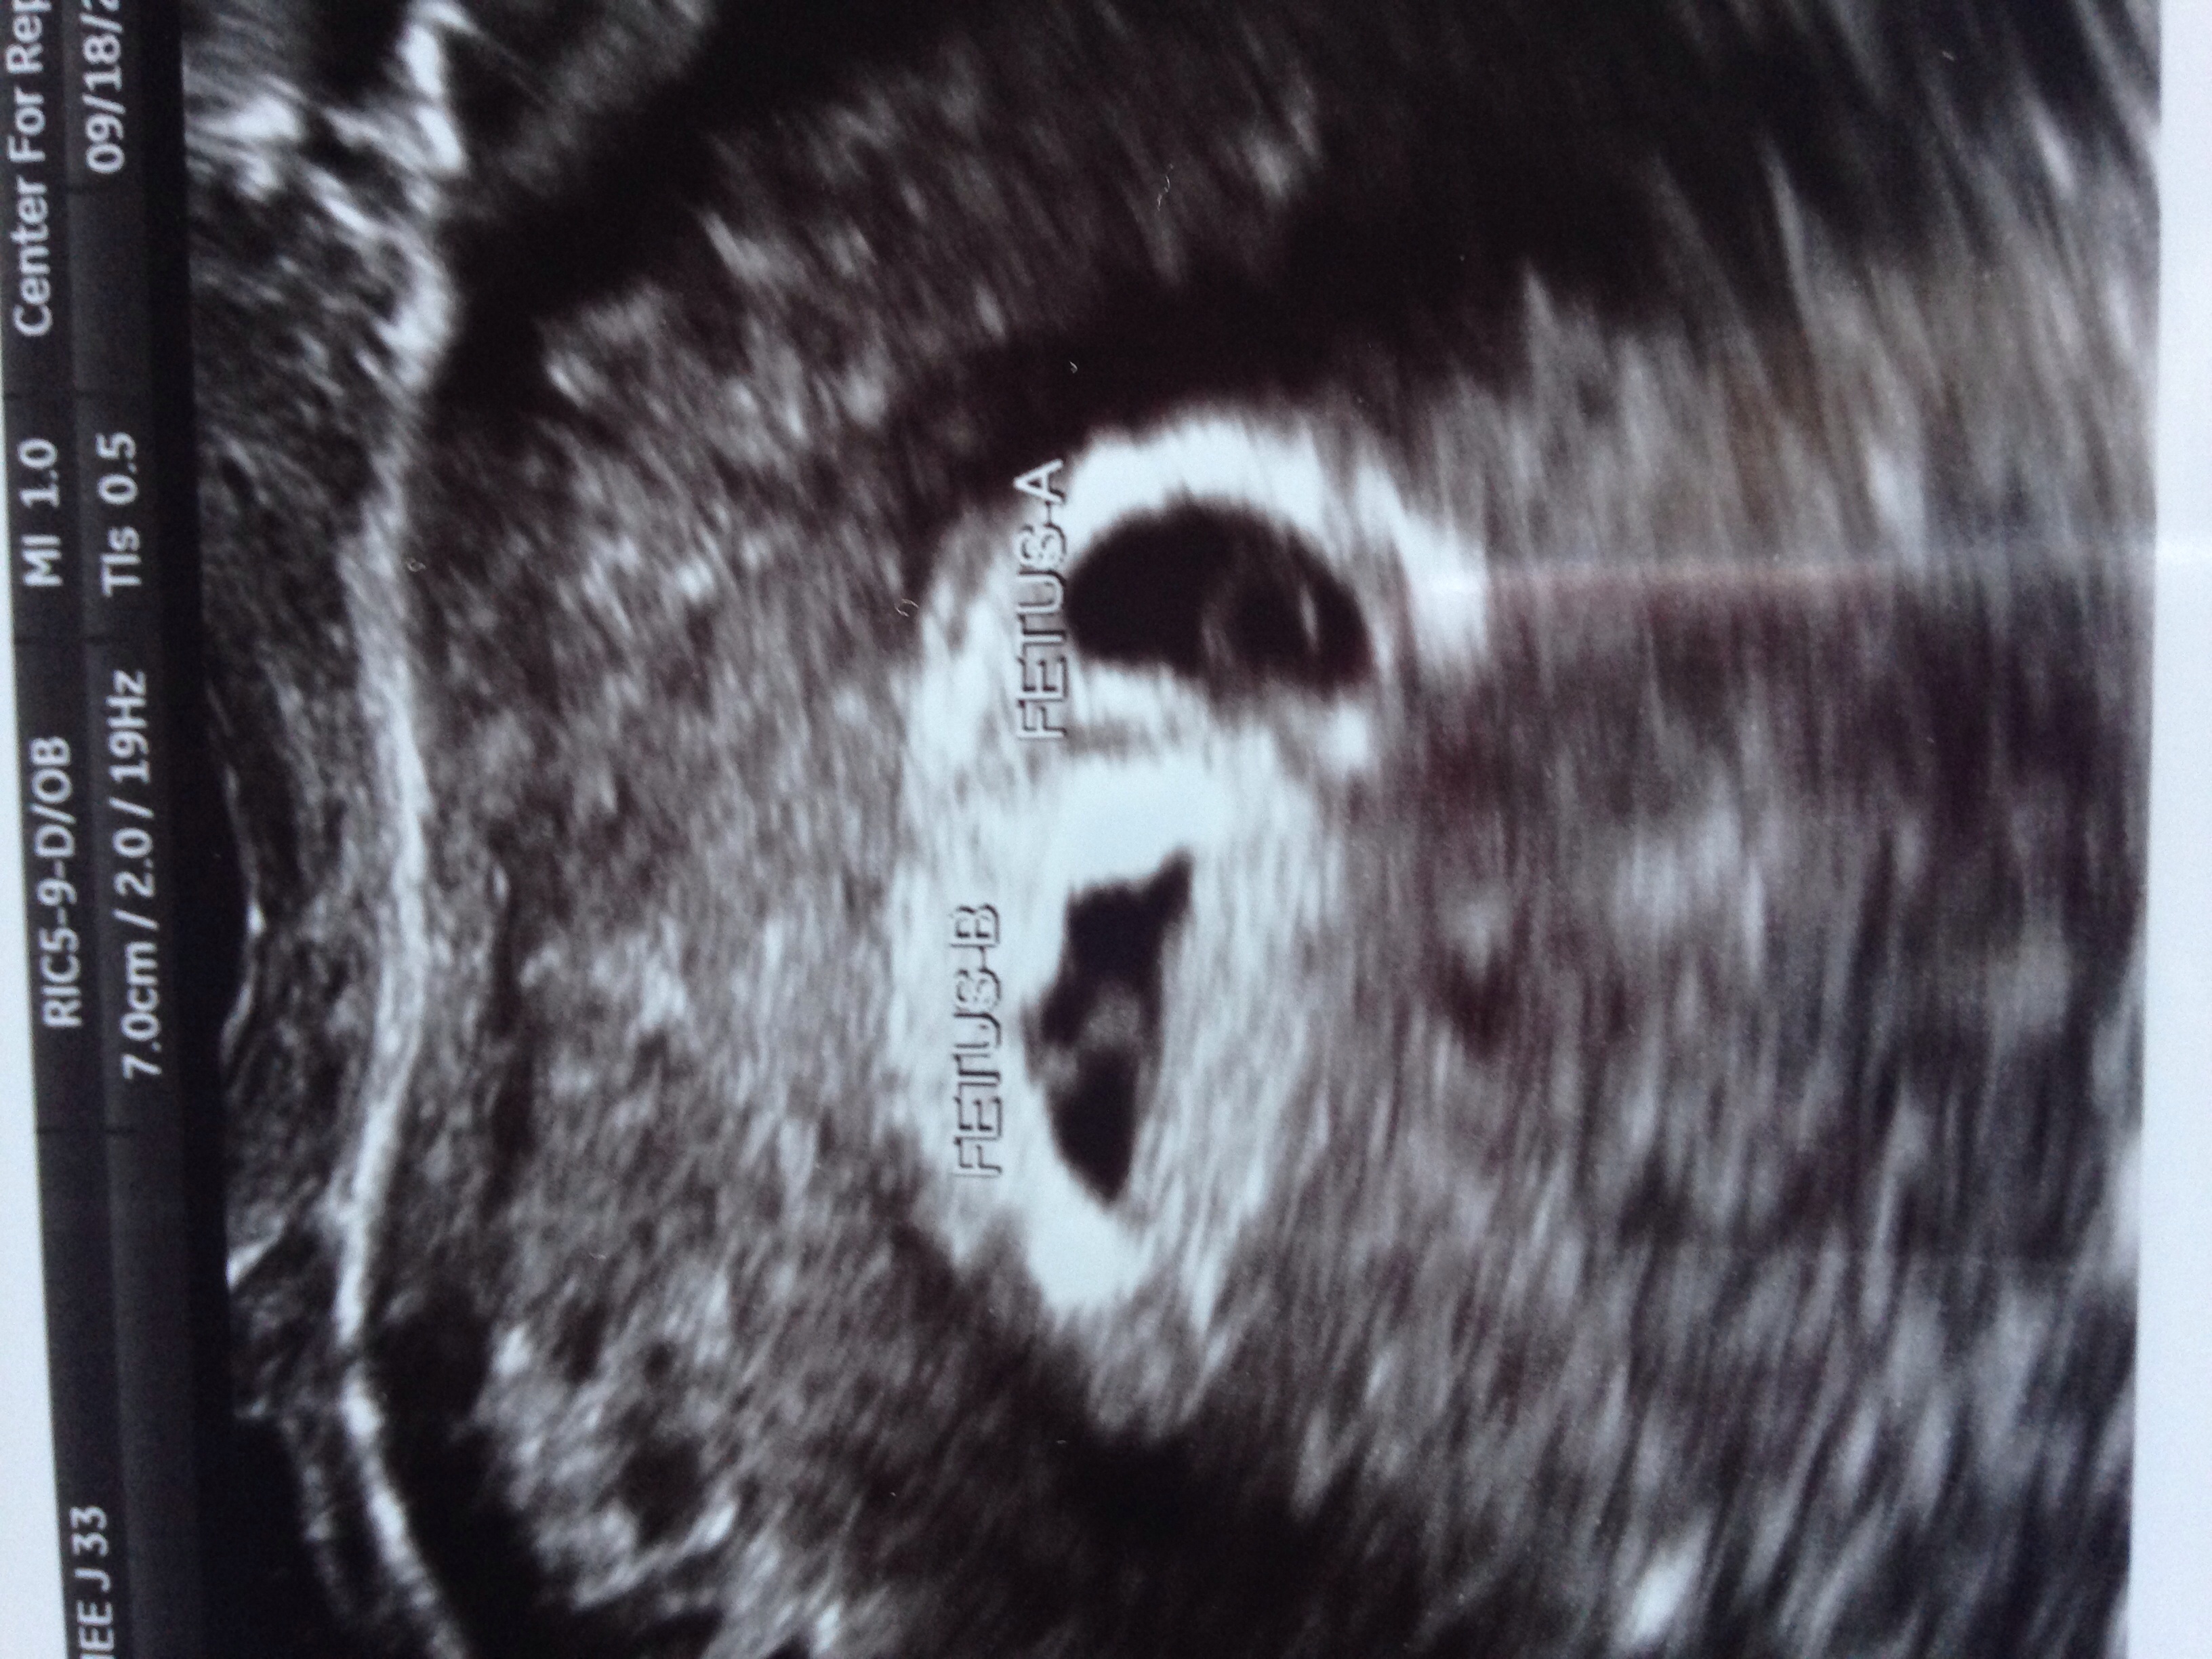

Listening to the sage advice of panderp, I went in for an ultrasound.

She couldn't find any cause of bleeding and thinks it may be coming from the aspirin I take.

She did find this though:

TWINS!!